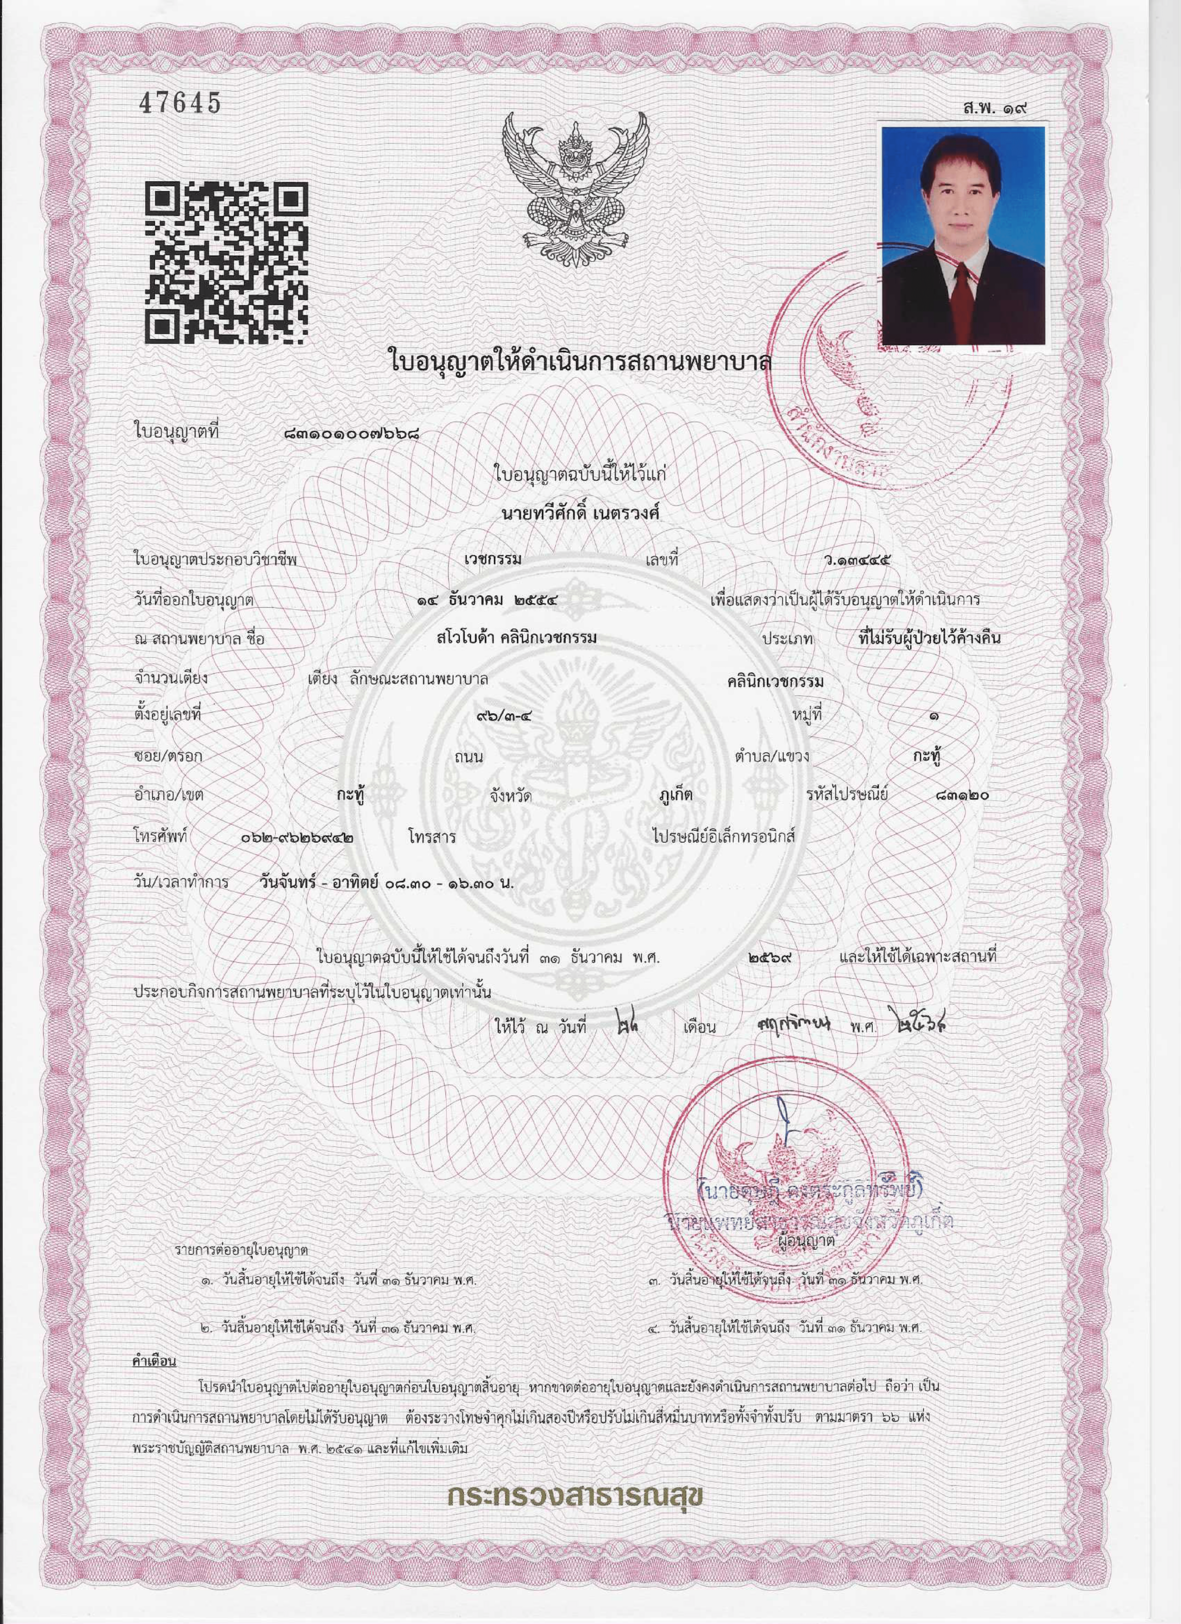

Quality you can trust

We are licensed by Thailand’s Ministry of Public Health and operate in accordance with local regulations. We follow high private-clinic standards, use certified medical-grade products, and our doctors have relevant training and experience. We focus on attentive service and consistently high-quality care.